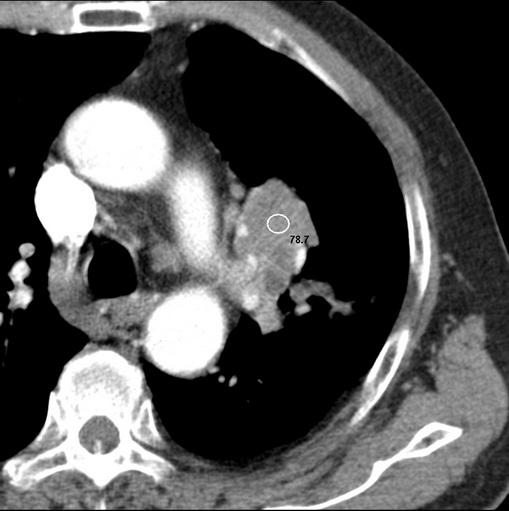

有强化 考虑肺癌肺门淋巴结转移

强化较典型,左上肺癌并纵膈淋巴结转移;左上肺结核并空洞形成;胸膜增厚.

肿块贴近左肺门,包绕左上肺动脉,形态不规则。肿块增强扫描中度强化。纵膈内主动脉弓左旁间隙、气管隆突前、下间隙见多枚淋巴结影。综上考虑左侧中央型肺癌可能性大。图片没有完整上传,尤其是左肺上叶支气管分支层面没有上传,因此不好判断是叶支气管中断还是段支气管中断。另外,下图红色部分所示是“黏液支气管征”吗?